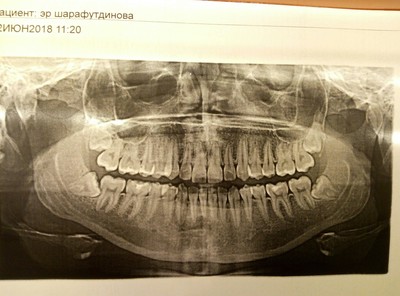

Вердикт после рентгена - удалять все 4, а сейчас мне предложили сделать разрез, чтобы не скапливалась еда под образовавшимся капюшоном. Я отказалась - через пару дней предстояли ГОСы, хотелось нормально разговаривать. Запись на 2 талона на раннее утро (удаление сложное, зубы "лежат") через 5 дней, пока поживу на обезболивающим. Как ни странно, оно не понадобилось, зубы болеть прекратили. Видимо, это было просто первое напоминание от зубов мудрости о себе.